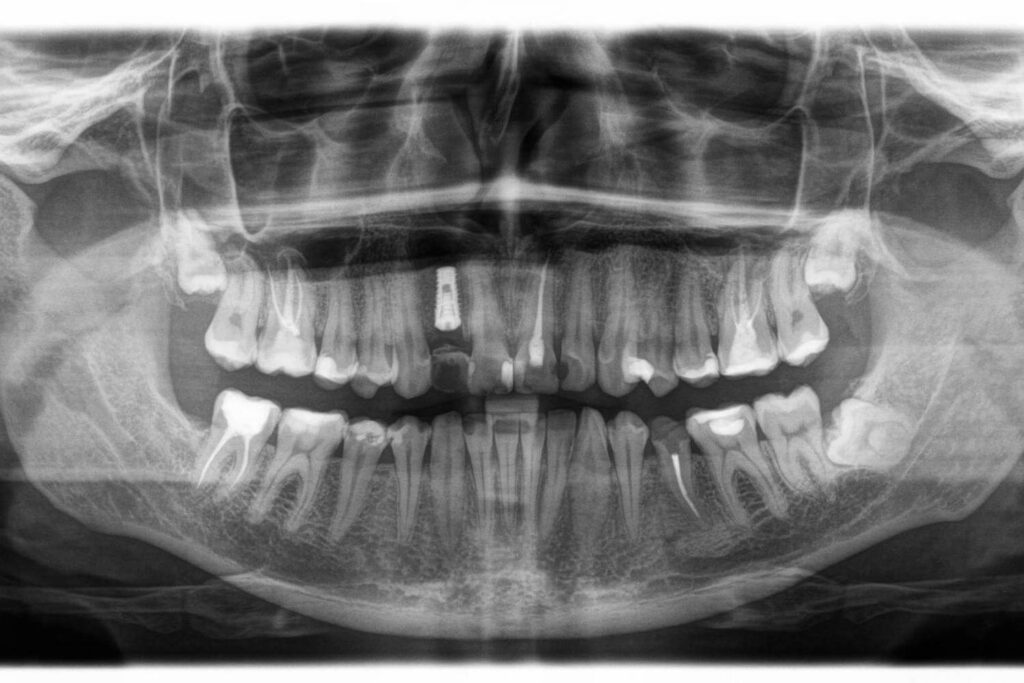

Нами было предложено следующее лечение: КТ диагностика с планированием лечения, эндоподготовка под протезирование фронтальных зубов верхней и нижней челюстей и обработка их под временные коронки, удаление жевательных (подвижных) зубов верхней челюсти с одновременной имплантацией и дополнительно установленные импланты на жевательные зубы нижней челюсти.

КТ-исследование